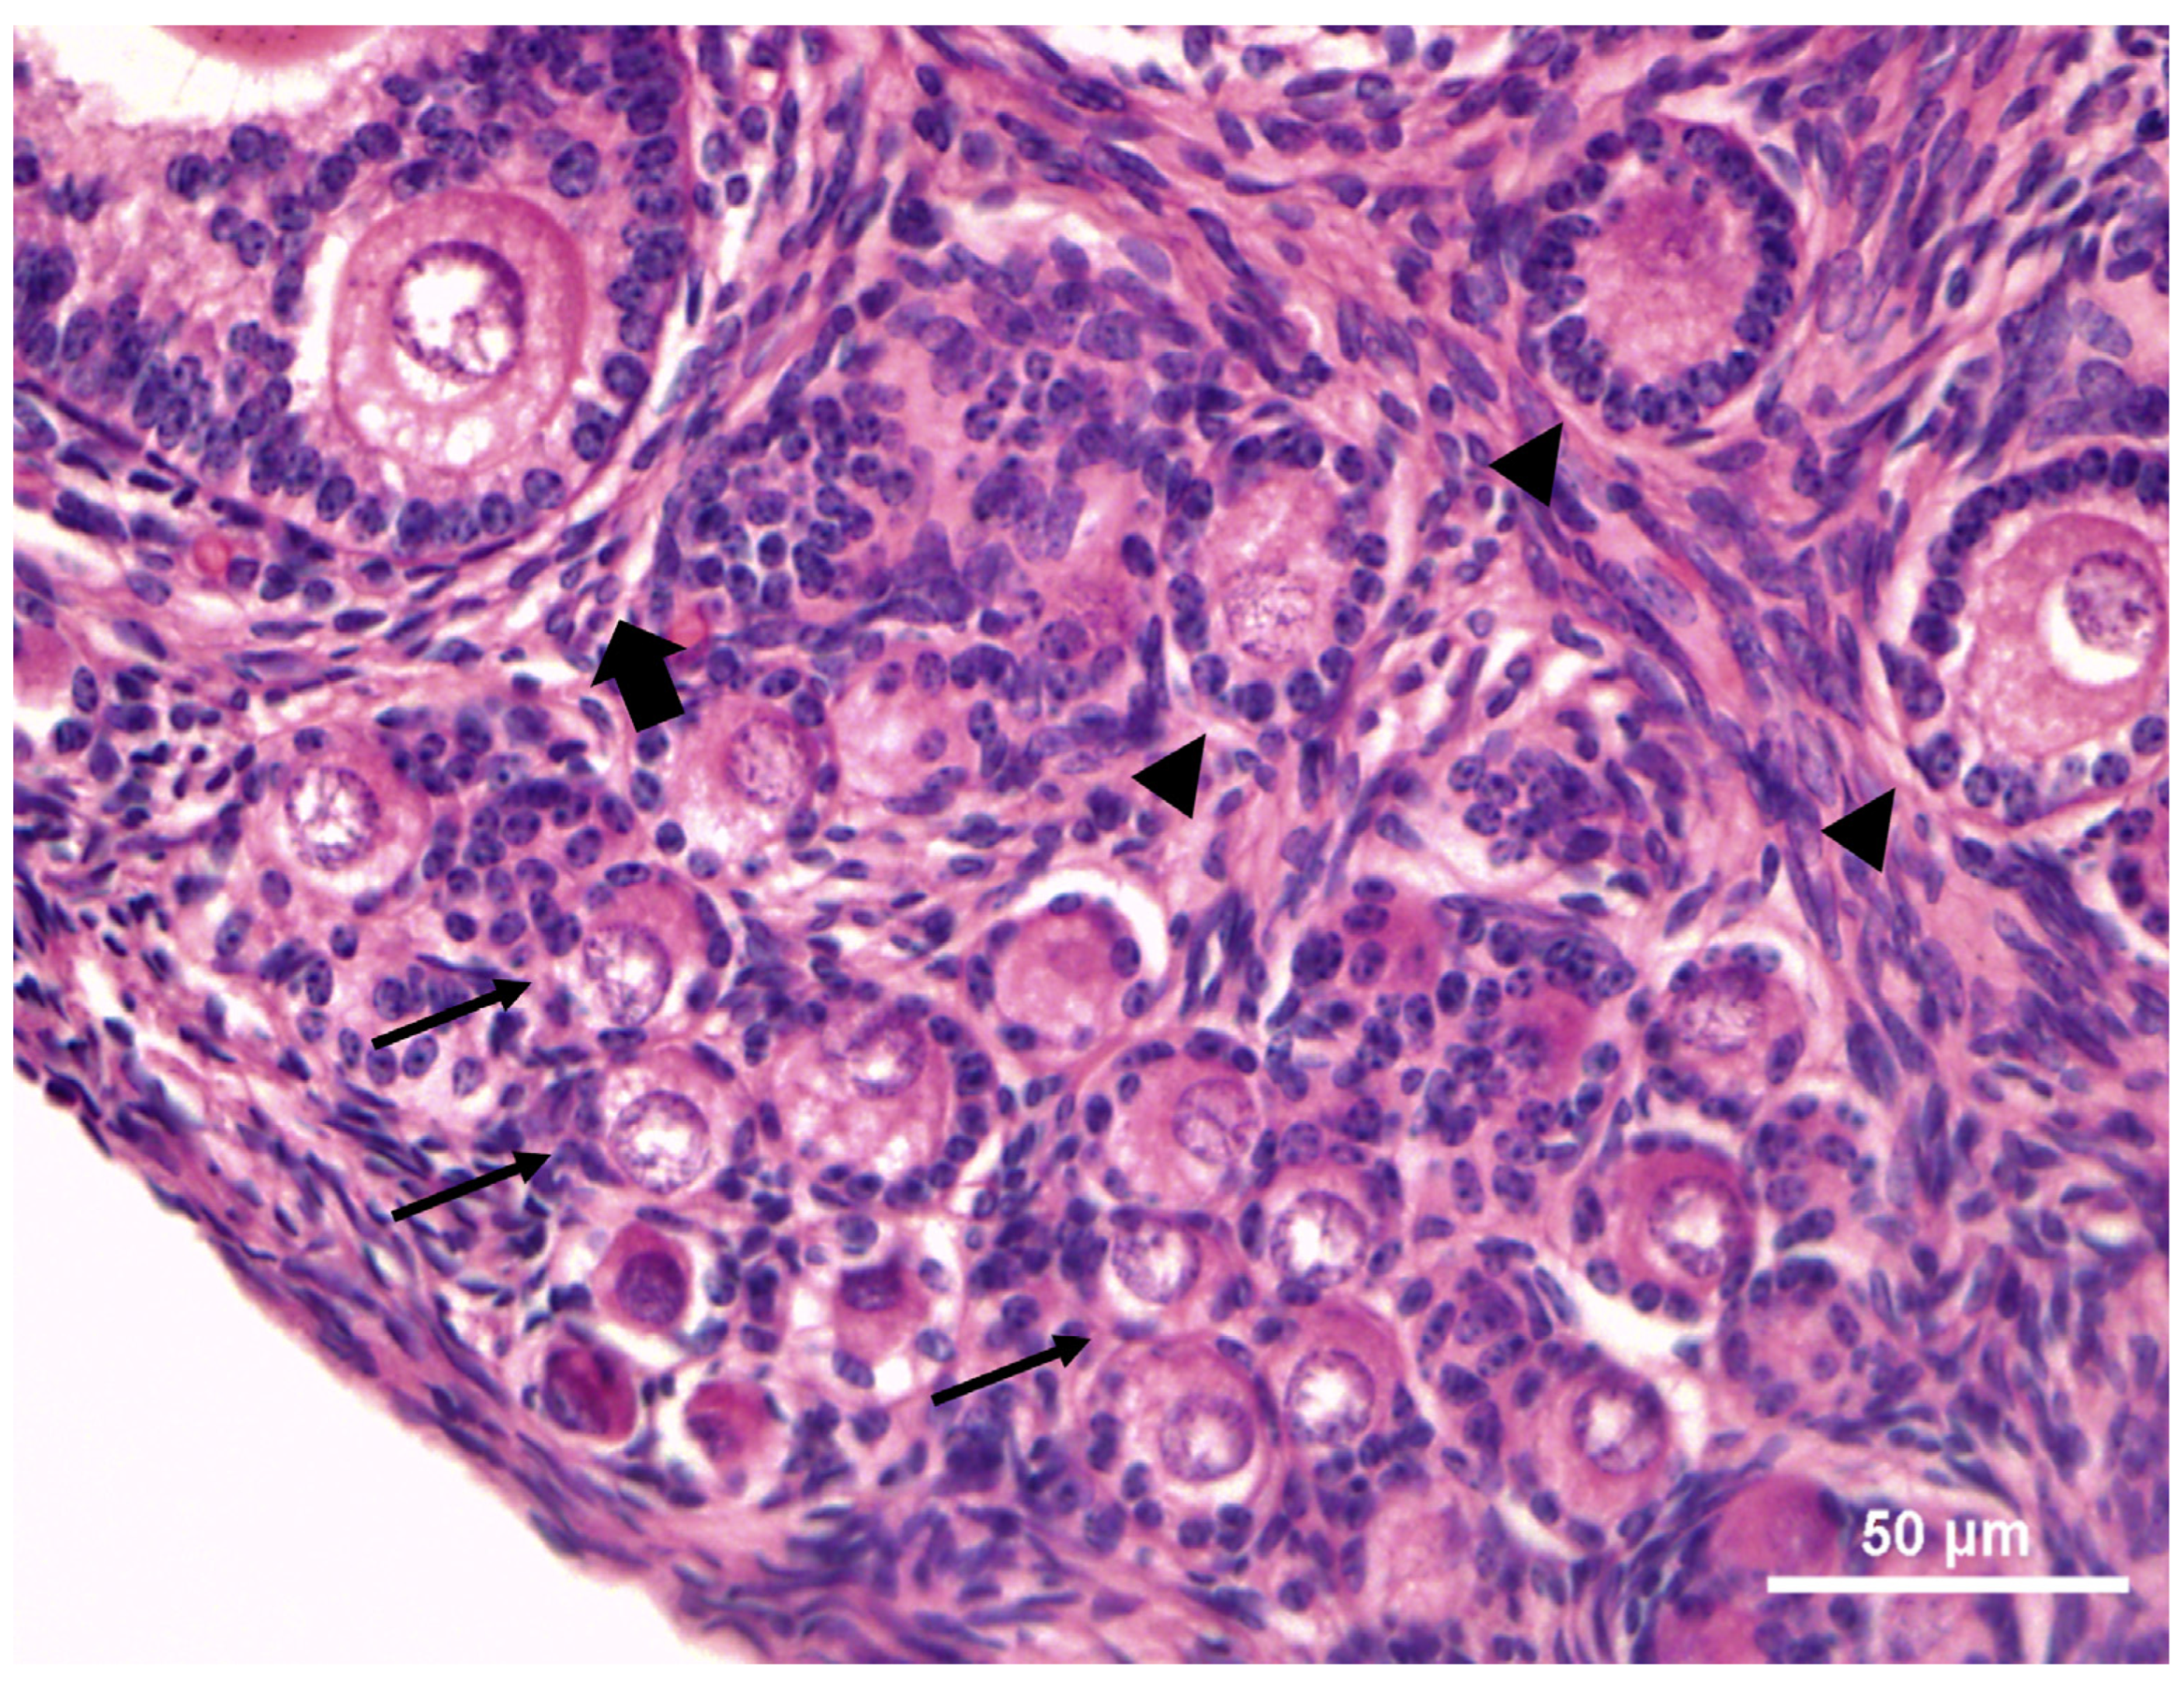

Primordial and primary follicles were characterized by an oocyte surrounded by a single layer of flattened or cuboidal granulosa cells, respectively (Figure 3a,b). Secondary follicles had two or more concentric layers of cuboidal granulosa cells around the oocyte. Externally of the granulosa cells, the internal theca was formed by elongated and fusiform cells, appearing as concentric layers. An evident zona pellucida was observed between granulosa cell layers and oocyte (Figure 3c). Oocytes presented heterogenic cytoplasm with some vacuoles. The nuclear membrane was visible. Scattered regions of chromatin and heterochromatin were located near the nucleus membrane. Multi-oocytes follicles (Figure 3d) were observed in all animals, near the germinative epithelium. Overall, a total of 4 to 150 multi-oocyte follicles per ovarian pair were observed (Table 2).

Morphologically normal PFs showed a spherical oocyte with an eosinophilic nucleus and heterogeneous cytoplasm. Granulosa cells without pycnotic nuclei were well-organized in layers surrounding the oocyte. Degenerated follicles showed a retraced oocyte with or without a pycnotic nucleus, accompanied or not by disorganized granulosa cells (Figure 4).

Figure 3. Histological features in the juvenile six-banded armadillos (Euphractus sexcintus) preantral follicles. (a)—Primordial follicles (arrows) surrounded by a single layer of flattened granulosa cells. (b)—Primary follicles (full arrows) surrounded by a single layer of cuboidal granulosa cells, presenting some vacuoles at cytoplasm. (c)—Small secondary follicle showing two or more layers of cuboidal granulosa cells (n—nucleus, c—cytoplasm, gc—granulosa cells) and the presence of zona pellucida (white arrow). The theca cells were formed by elongated and fusiform cells (white arrowheads). (d)—multi-oocyte follicles (arrowheads). 400×.

Figure 4. Morphological normal follicles (arrows) exhibiting well-organized granulosa cells without pycnotic nuclei surrounding the oocyte. Degenerated follicles (full arrows) showing a retraced oocyte with a pycnotic nucleus, accompanied or not by disorganized granulosa cells. 400×.